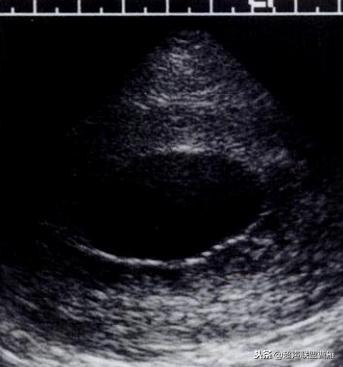

· 是妊娠囊内超声能发现的第一个解剖结构。是宫内妊娠的标志。

· 正常情况下,卵黄囊中央表现为无回声,周边为厚薄均一、边界清晰的环形高回声。

妊娠37天超声检查卵黄囊可以显示,羊膜腔及胚胎不能显示

真实的卵黄囊、胚体及羊膜腔形象

妊娠37天出现卵黄囊

在妊娠妊娠38天前后(36-40)天可以见到卵黄囊。 孕囊在6-9mm的可以见到其中有卵黄囊。